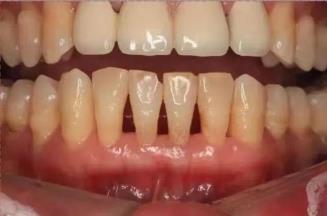

如果有过上述情况,那么大概率是您的口腔健康情况出现了问题。正常情况下我们牙龈是呈现粉红色,无肿胀出血情况,而在炎症情况下表现为鲜红或暗色,水肿松软,甚至出血、流脓。

牙周炎可发生于任何年龄,大多数为成年人,男女性别无差异,由于细菌菌斑的累牙龈出现炎症,病情的变化也会随着时间累逐渐加重。表现形式初期明显表现为牙龈出,随之伴发出现口臭、牙周脓肿、牙龈退缩牙根敏感、牙齿龋坏、食物嵌塞、逆行性牙髓炎、牙松动或移位甚至脱落。